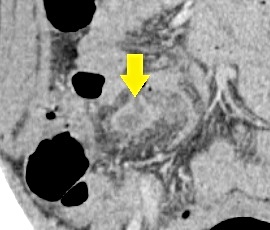

急性腹症のため救急受診。精査の結果、急性虫垂炎および限局性腹膜炎と診断。緊急手術(腹腔鏡下虫垂切除術)を施行した。病理結果は急性虫垂炎であった。

CT画像